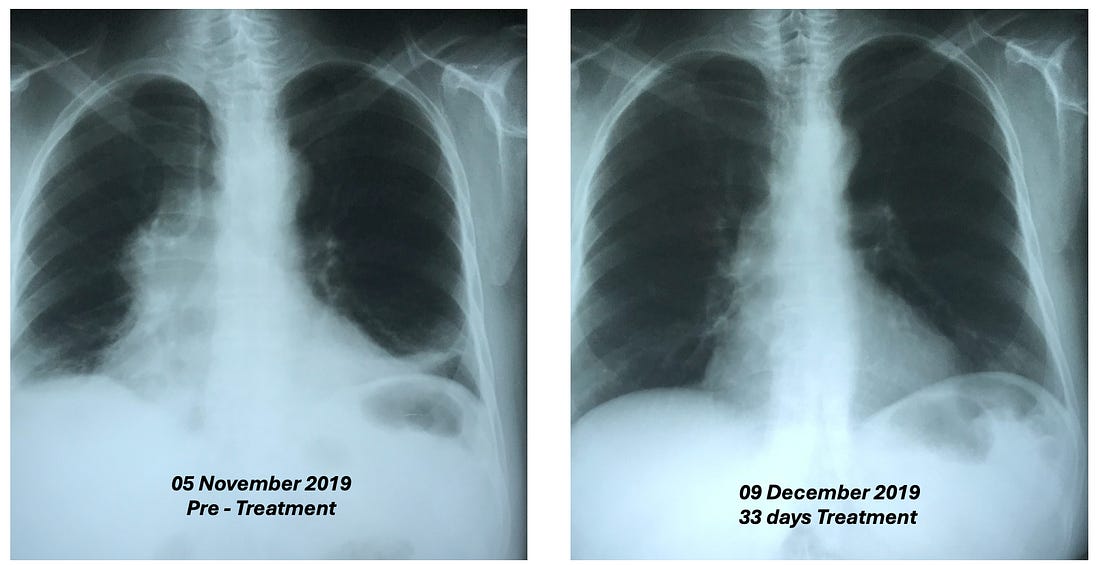

advice). •He felt very strongly about the necessity of chelation therapy in cancer (e.g., to prevent subsequent heart attacks following successful D-hematoxylin treatments—which occurred years later in some of Tucker’s cases) and to that you should not give leukemia patients with anemia iron as the cancer needed that to grow (to the point he would sometimes also chelate iron in leukemic patients). •McCann was also very focused on cultivating bacteria on a target media that would dissolve specific biological targets (e.g., he cultured bacteria from a dead cow’s cataract and then found it could eliminate other cataracts; likewise, he found this approach worked for cancer). Note: my experience with individuals like McCann is that some of their insights are spot on while others they have a deep conviction in are ultimately not correct. The Next PhaseLike many alternative therapies, D-hematoxylin grew up in “the Wild West” of alternative medicine. This was made possible by its very low toxicity profile, which allowed it to be used in humans at widely varying doses without significant side effects. Fortunately, the threads keeping D-hematoxylin from being lost eventually converged in Ecuador with a doctor who’d successfully treated 44 out of 45 cases of microbiologically confirmed chronic bacterial prostatitis using DMSO combined with antibiotics that were applied directly into the bladder (much in the same DMSO is FDA approved to treat interstitial cystitis) who then tested negative for any infection 15-20 days following treatment (with no subsequent recurrences), demonstrating DMSO's ability to counteract bacterial resistance. Note: interestingly, Stanley Jacob, was still alive when these treatments were initiated (he died in 2019 at age 91). At the start of the prostatitis treatments, the doctor in Ecuador contacted him for advice, and Jacob encouraged the experiment, agreeing it was a good idea, even though he hadn't heard of anyone attempting it before. As he’d heard of McCann through Ecuador’s medical community, these prostatitis successes inspired that doctor to try intravesical DMSO mixed with hematoxylin for a prostate cancer patient (which was administered in the same manner and frequency as his prostatitis treatments). This worked, and he gradually began using it for other prostate cancer patients and then other cancers as well, which gradually grew into a fifteen-year research project on the therapy (which he's shared with me over the course of a few months). Note: I also know of one individual who used D-hematoxylin intrarectally over a prolonged period to locally treat a cancer there, but the data on this approach is still limited. Recent D-Hematoxylin PatientsThat

project involved treating approximately 85 patients, with the cure rate

in patients who had not previously received chemotherapy averaging

between 80-90%. As such D-hematoxylin is an excellent cancer treatment

but it is not perfect and will not work for everyone. •Leukemias (particularly acute leukemia) Note: myeloproliferative neoplasms (e.g., polycythemia vera, essential thrombocythemia and primary myelofibrosis) depend upon a mutant protein for survival which was shown to be susceptible to disruption by a few small compounds including hematoxylin. While D-hematoxylin has not been tested on these disorders, this study (along with the other known effects of DMSO and D-hematoxylin) suggest it could be an effective treatment for them. The cancers with a poorer response included: •“Solid” tumors Additionally, if there is a cancer marker associated with the tumor (e.g., CEA or PSA), it will often rapidly drop, making it very easy to track the progress of D-hematoxylin. As the following cases show, many of the improvements were quite profound: •A 54-year-old female patient with Classic Hodgkin Lymphoma which had invaded 72% of her bone marrow, with CD20-positive expression. She had a variety of symptoms (e.g., recurrent pleural effusions and anemia), but since her religion did not permit blood transfusions, she received only D-hematoxylin and EDTA and then had a full recovery (with no recurrence in twelve years of follow up). The most striking aspect of this case was the change in her bone marrow biopsy, after three months of treatment with D-hematoxylin (unlike chemotherapy) it selectively destroyed the cancerous cells, allowing normal ones to regrow and rapidly addressed her anemia. •A 72 year old patient with leukemia who was anemic and had her anemia rapidly improve following D-hematoxylin: Likewise, similar bone marrow changes were seen in her. Note: another similar leukemic patient on D-hematoxylin with anemia had no improvement. After investigating, it was determined this was due to her regularly using WD40 on a daily basis (without respiratory protection) and hence having a bone marrow intoxication which was directly damaging the bone marrow (and in turn the leukemia diagnosis may have been incorrect). •A 16 year old male with a mediastinal seminoma that received 16 D-hematoxylin infusions, 5 IV vitamin C infusions and then one chemotherapy session (on July 7) where cisplatin and bleomycin were combined with DMSO (after which he continued chemotherapy and has recovered from the cancer). •A 63-year-old male with cholangiocarcinoma (a rare, aggressive and notoriously difficult to treat cancer of the bile duct) who received D-hematoxylin plus chelation and vitamin C (but no chemotherapy). During his successful treatment, a drain from his bile duct was also monitored for tumor markers. Additionally, the cancer debris could be seen in the drainage tube (an internal-external percutaneous transhepatic biliary drainage catheter)—something which the Ecuador doctors now view as essential to have if D-hematoxylin will be used in this cancer: Note: another bile duct cancer patient (a 68 year old female) received palliative D-hematoxylin while waiting for surgery and chemotherapy (which ultimately could not be done because of how advanced the cancer was). Her cancer markers levels significantly improved following D-hematoxylin (and continued to reduce during gaps in treatment), but she eventually lost the will to live and passed after 16 months. •A 63-year-old man with B-cell lymphoproliferative disorder who received D-hematoxylin for 10 days (with no other treatment), experienced a significant drop (normalization) of his white blood cell count during that time then stopped at the advice of his hematologists, and two years later died from COVID. •A man who had a stable bladder polyp which became cancerous following a covid vaccination (with the initial sign being a large blood clot in the urine) which when examined had spread in a large portion of the urinary tract’s endothelium. It was surgically removed, but due to how far it had spread, the urologist told the patient he would only survive for two months. They then began five weeks of intravesical and IV D-hematoxylin, and in four years, the cancer never returned (which led to the urologist telling everyone about the “amazing” surgical procedure they had performed). •A 55-year-old female who had a mediastinal tumor (type unknown as it was wrapped 560° around the aorta and hence could not be biopsied) which fully resolved after 33 daily D-hematoxylin treatments. Additionally, this was the CT prior to treatment where the tumor can be seen around the aorta: While this was the CT two weeks following the D-hematoxylin treatment: Lastly, at five years follow up, there was no recurrence. •A 27-year-old female with acute lymphoblastic leukemia reacted poorly to two sessions of chemo, was classified as terminal, and then was started on D-hematoxylin. She had a significant improvement in her cancer and simultaneous improvement in her anemia which continued long after conventional treatments for anemia were halted (which did not include blood transfusions as she was a Jehovah’s Witness). In a before (1-2-2020) and after (2-1-2020) video I saw of this patient, she initially looked very frail and had difficulty walking, while just a month later (after 31 days of treatment), she had no difficulty walking and looked vibrant and robust. Additionally, they continued to monitor her on a monthly basis, and four years later, she’d had a healthy baby, and had her hematocrit range from 42 to 48 (which is slightly above average) indicating she had no further risk of anemia (even though hematologists in the hospital had predicted her reckless pregnancy would cause severe anemia). Additionally, her ESR (which had been significantly elevated prior to treatment) normalized (and remains normal 5 years later). Lessons from EcuadorIn addition to observing a remarkable degree of success from D-hematoxylin, the Ecuadorian team was able to discern a variety of patterns (many of which mirrored Tucker’s previous observations) that helped craft their treatment protocols. For example: •While DMSO alone can somewhat help with cancer, the effects of DMSO combined with hematoxylin are completely different from what would be observed with DMSO alone. •They saw many signs during their treatment protocols that D-hematoxylin selectively targeted cancer cells. •Cancers did not develop resistance to D-hematoxylin (which is a common challenge with many chemotherapies). •While some tumors rapidly disappear, other types frequently become avascular (which stops their growth) and dried-out, blanched, or fibrous rather than being directly shrunk (e.g., I reviewed cases where a brain cancer simply stopped growing). In many cases, those tumors are then very easy to extract surgically. Note: to my knowledge, everyone besides that Ecuadorian team who treats with D-hematoxylin still uses Tucker’s protocol and has not tried to improve upon it. Variations in D-Hematoxylin EfficacyOn